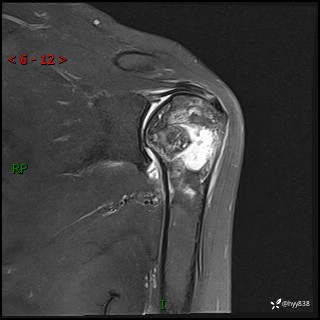

肱骨MRI平扫(axi T1WI+cor T2WI-fs)+CE-fs(COR+SAG)